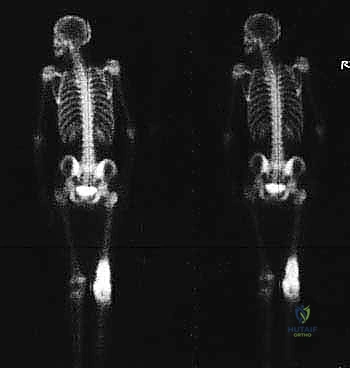

- المسح الذري للعظام (Bone Scan) والتصوير المقطعي بالإصدار البوزيتروني (PET Scan): للتأكد من عدم انتشار الورم إلى أجزاء أخرى من الجسم.

معرض الحالات الإشعاعية: توثيق النجاح الطبي مع د. محمد هطيف

الصور الإشعاعية قبل وبعد الجراحة هي الدليل القاطع على دقة ونجاح الإجراء الطبي. نستعرض هنا مجموعة من الصور التي توضح حجم الإنجاز الطبي في استبدال العظم المصاب بمفصل معدني متطور.